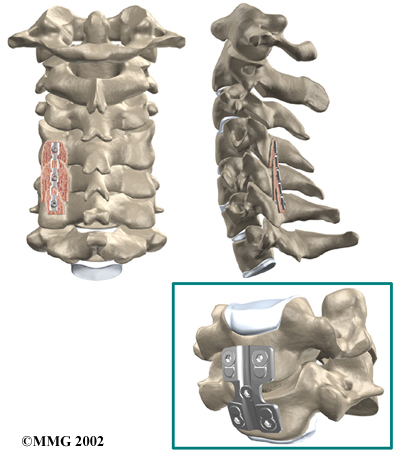

Cervical Fusion

A fusion surgery joins two or more bones into one solid bone. The purpose for doing spinal fusion is to increase the space between the vertebrae and to keep the sore joint from moving. This is usually done by placing a small block of bone graft in the space where a disc was removed. Opening up more space enlarges the neural foramen, takes pressure off the nerve roots, and eases tension on the facet joints. Cervical fusion is used to treat neck problems such as cervical radiculopathy, disc herniations, fractures, and spinal instability. There are two main types of fusion for neck problems.

- Anterior Discectomy and Fusion: Anterior discectomy and fusion is done through the front of the neck. After taking out the disc (discectomy), the disc space is filled with a small graft of bone. The bone is allowed to heal, fusing the two vertebrae into one solid bone.

The bone graft needs time to heal in order for the fusion to succeed. This requires the neck to be held still. After cervical fusion surgery, patients usually have to wear a special neck brace for several months. These neck braces are often bulky and restrictive. Recently, surgeons have begun using metal plates and screws (often referred to as instrumentation) to lock the bones in place. The instrumentation is fastened to the vertebrae, where it holds the bones still while the graft heals.

Locking the Bones in Place